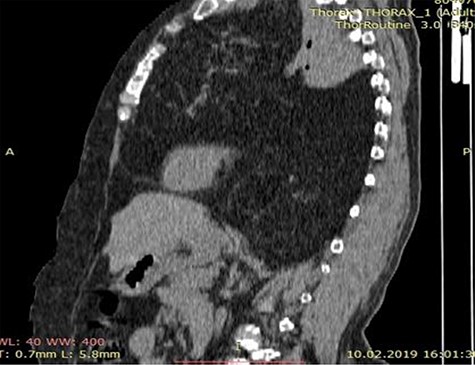

A 60-year-old female patient presented to the emergency with complains of dyspnea, non-productive cough and chest pain for 2 months. There is no history of hemoptysis, weight loss and substance abuse. On physical examination, oxygen saturation was 64%, blood pressure was 170/110 mm Hg, temperature was 97.9°F (36.6°C) and blood sugar was normal. Local examination of the chest revealed limitation in chest movement and decreased tactile focal fremitus on both sides of the chest. On percussion, dullness on both sides of the chest was noticed. On auscultation, decreased breath sounds on both sides of the chest were detected and the apex beat of the heart was displaced on the right side. The blood tests performed in the emergency room were in normal range. She underwent radiological evaluation with chest X-ray that revealed diffuse infiltration on both lungs (Fig. 1). Thoracic echocardiography revealed huge mediastinal mass with dextrocardia. This was followed by chest computed tomography (CT) that showed bilateral diffuse mediastinal mass, which involves fatty tissue containing soft tissue streaks that probably represent islands of normal thymic components with no infiltrations (Figs. 2–3). We concluded that the only curative treatment of thymolipoma is surgical excision. Unfortunately, despite the patient being told about the surgical procedure, she did not give the permission and passed away a week later due to secondary compression to the lungs.

Axial chest CT image showing a mass lesion with wide range of fat density filling both hemithorax was observed, including linear and nodular densities in the right hemithorax. A dense retrosternal mass displacing both lungs and chest. No evidence of invasion is seen.

CT scan of the chest showing a large anterior mediastinum mass projecting to the right and left hemithorax with wide range of fat tissue density.